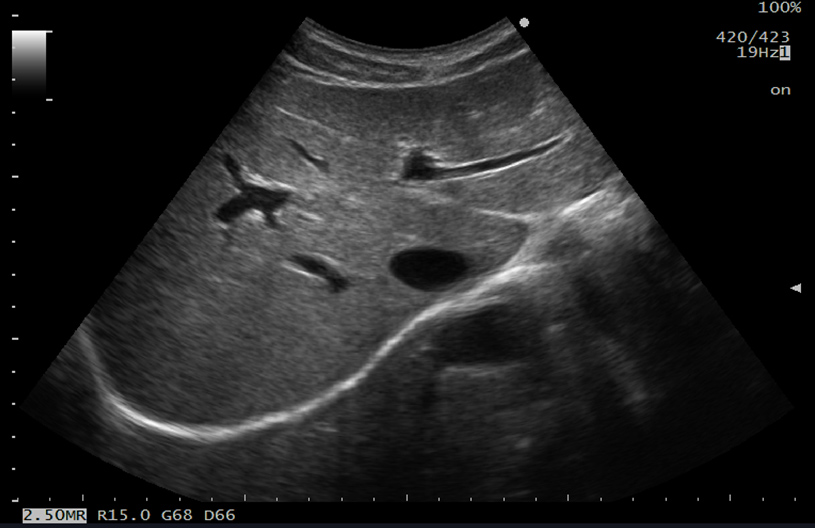

This adaptive image filter has further evolved to reduce speckles and boost edge enhancement, generating clearer images for easier interpretation.

Enhances visualization of tissue boundaries and reduces artifacts. Ultrasound beams are transmitted in multiple directions to scan the object from different angles. These scans are superimposed in real time, improving contrast resolution and reducing speckles, thus allowing clearer observation of lesions.